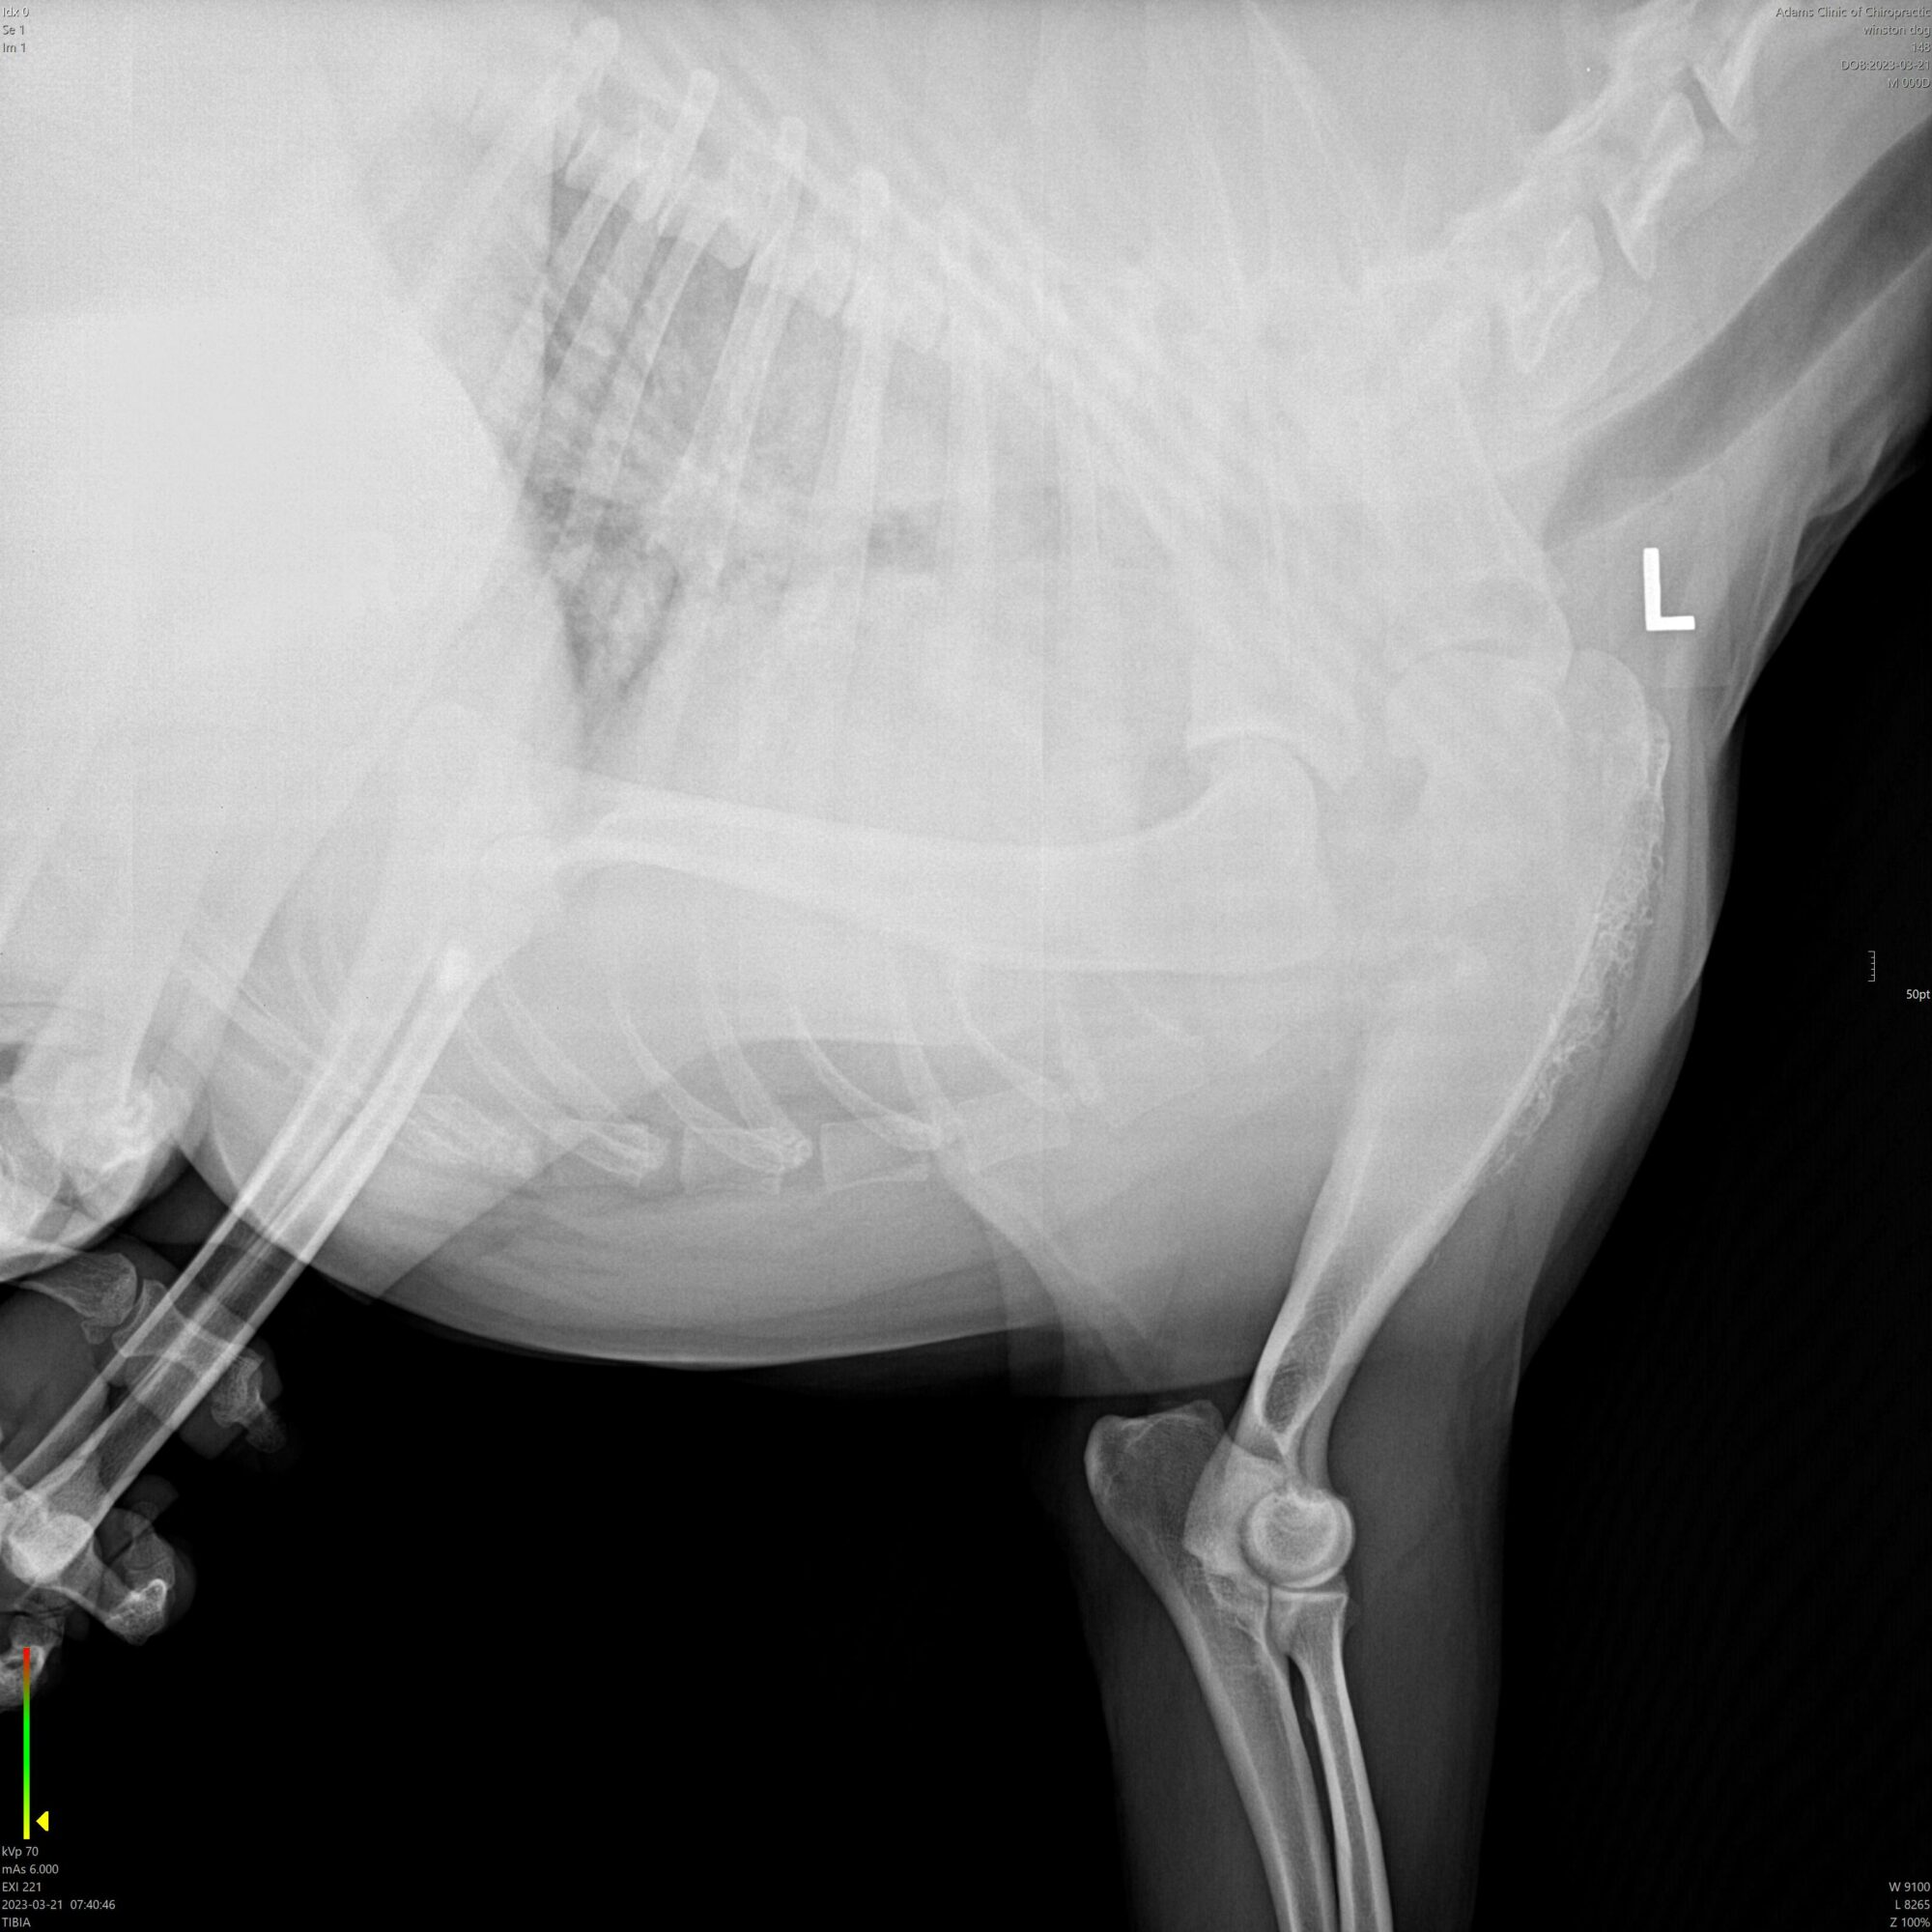

Bone cancer. How could he have bone cancer? He is only 4 years old. He has a great pedigree. He has nothing like bone cancer in any of his family history. We have been doing ministry together for 3 of his short 4 years of life. He cannot have bone cancer! Yet, there it was on the large screen in front of him. The Vet he had been referred to is close friends with the Oncology Department Head at the local university. They had conferred and he had agreed 100%. It was advanced and it was aggressive. “Act now or lose your dog in weeks. They can take him tomorrow at the university but that will cost ten to twelve thousand dollars. Or, we can remove the leg tomorrow. That will cost about four thousand,” the vet told him flatly.

In a split second, Tim thought he heard in his heart that “still, small voice” that people talk about. He was reminded of a story he had heard a decade or more before in which God had fixed a man’s guitar. The entire story flooded back to him in an instant and he thought he heard God say, “If I care enough about a man and his guitar, then I care enough about a man and his dog.” That was it. Wait. That was it? God, can’t you be a little more specific? Can’t you write on the wall or something? Does that mean you’re going to heal Winston or does that mean…. what does that even mean?

Tim turned to the Vet. “I believe I have another option.” Shocked and obviously offended she just stared at him as if he were an idiot. The unspoken question of “what is it?” was written all over her face. “I believe God is going to heal my dog,” he told her. He could hardly believe the words had even come out of his mouth. Was he crazy or just stupid? He didn’t know which, he just thought he had heard from God and that was all he had. Her stare changed to slight disappointment as if he were some pathetic soul. “…if that’s what makes you feel better,” she said condescendingly.